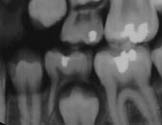

When all postmortem examinations have been done, comparisons between the ante- and postmortem examinations must be done. During this procedure it is of great value to have access to an identification program with a possibility to register all examinations. I have described this procedure in a foregoing message, by means of such a program a first matching of the ante- and postmortem examinations can be done. It is useful here to use an international program if several different countries are involved, and such a program has been constructed by means of the international police organisation-Interpol. Often, especially if there are only antemortem radiographs available, the same radiographs must be taken postmortem. In an example downunder you can see the antemortem radiograph to the left and the postmortem to the right.

Image 1Image 2

The victim in this case was a child, who was a passenger in a bus who crashed against a mountain side in Norway 1988. A very safe identification could be established by means of the radiographs. In fact, intraoral radiographs is one of the most accurate identification methods.